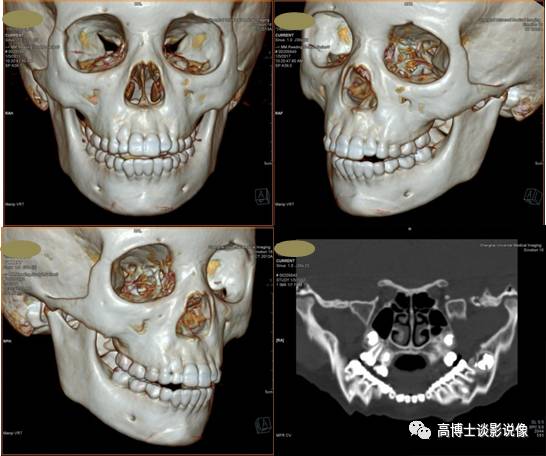

一、口腔颌面部VRT骨重建

全容积VRT重建可多方位显示骨骼全貌,了解颞颌关节、下颌管、牙槽骨等结构及邻近颌面骨、软组织、大血管等其他重要结构情况。

CPR曲面重建可整体显示牙槽骨全景图像,直观显示骨质结构及与周围重要结构间的关系。

二、下颌骨肿瘤CT三维骨重建

全容积VRT重建可观察肿瘤全貌,了解颌骨来源肿瘤部位、形态、大小;了解骨质破坏的类型、性质、程度、边界及骨膜反应等情况;了解肿瘤与周围结构如牙齿、下颌骨、牙槽骨、软组织、大血管间关系;了解有无异常供血动脉,为颌骨肿瘤的定位、定性诊断及选择治疗方案等提供依据。

以上两个作品对于不学医的朋友来说相当恐怖吧,通过计算机后处理技术把头部软组织去除后,剩下的头骨就是俗称的“骷髅头”了,医生们就是根据上面的CT重建信息来观察解剖结构和病灶及其周围情况的。